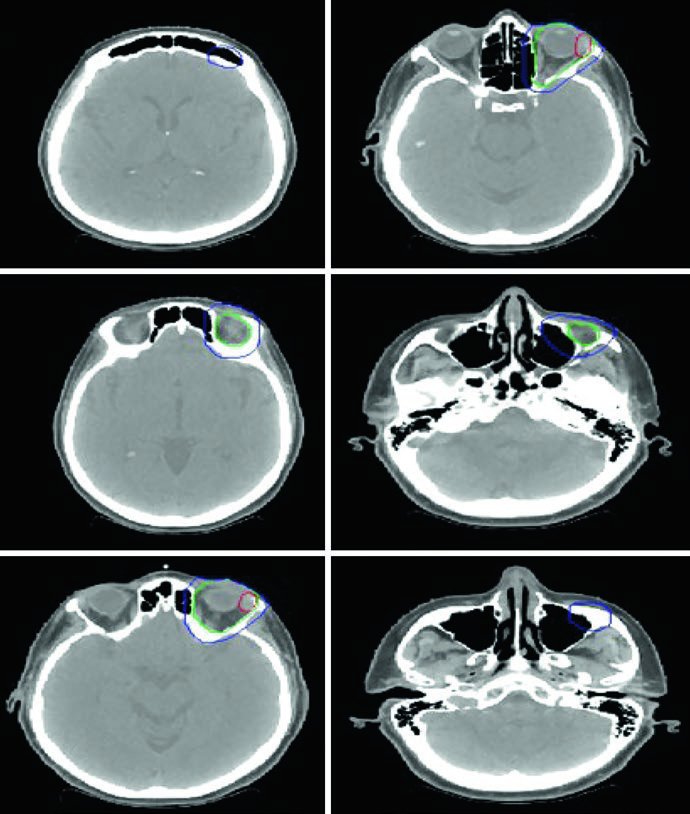

ISRT delineation for nodular lymphocyte-predominant Hodgkin lymphoma stage IIA with right supraclavicular, subpectoral, and axillary disease treated with definitive RT

Figure 31.3 — NLPHL stage IIA: GTV (red), ISRT CTV (green), and PTV (blue) with definitive RT. Source: Target Volume Delineation and Field Setup, 2nd Edition

Nodular Lymphocyte-Predominant HL (NLPHL)

A 61-year-old man with stage IIA NLPHL involving right supraclavicular, subpectoral, and axillary nodes was treated with definitive RT alone. Simulated with arms up using a wingboard. The diagnostic PET was fused to the simulation CT. As RT was the sole modality (no chemotherapy), more generous CTV margins were necessary to cover potential subclinical disease.

Diffuse Large B-Cell Lymphoma of the Head and Neck

Axial slices of PET-CT and simulation CT showing ISRT delineation for diffuse large B-cell lymphoma of the left tonsil and neck level 2

Figure 31.4 — DLBCL of tonsil and neck: pre-chemo GTV (red), post-chemo GTV (red), and ISRT CTV (green) covering the involved nodal level. Source: Target Volume Delineation and Field Setup, 2nd Edition

A 47-year-old woman with stage IIA DLBCL of the left tonsil and left neck (level 2, 5.6 cm) received 3 cycles of R-CHOP followed by consolidation RT. Simulated with neck in extension, immobilized with 5-point aquaplast mask. The ISRT CTV covers the entire left tonsil and left neck nodal level, including 1–2 cm superior and inferior to the pre-chemotherapy disease extent. Head and neck lymphoma cases require meticulous attention to registration between diagnostic PET and simulation CT.